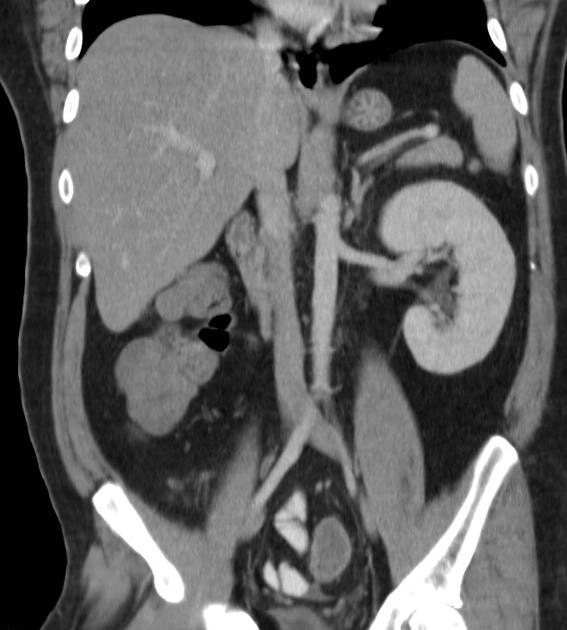

Thận móng ngựa (Horseshoe kidney)